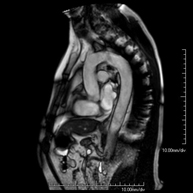

- RM Pelvis femenina

Prueba diagnóstica no invasiva que consiste en la obtención de imágenes de alta definición anatómica de la pelvis mediante el empleo de un campo electromagnético y ondas de radio (con un emisor y un receptor). No utiliza radiación ionizante. Se realiza para estudiar patologías del útero, del ovario, de las trompas y la vagina, ya sean de origen tumoral, inflamatorio o vasculares. Además permite valorar les estructuras adyacentes localizadas en la pelvis, identificando sus alteraciones. A veces requiere el uso de contraste intravenoso (Gadolinio) para caracterizar las lesiones.